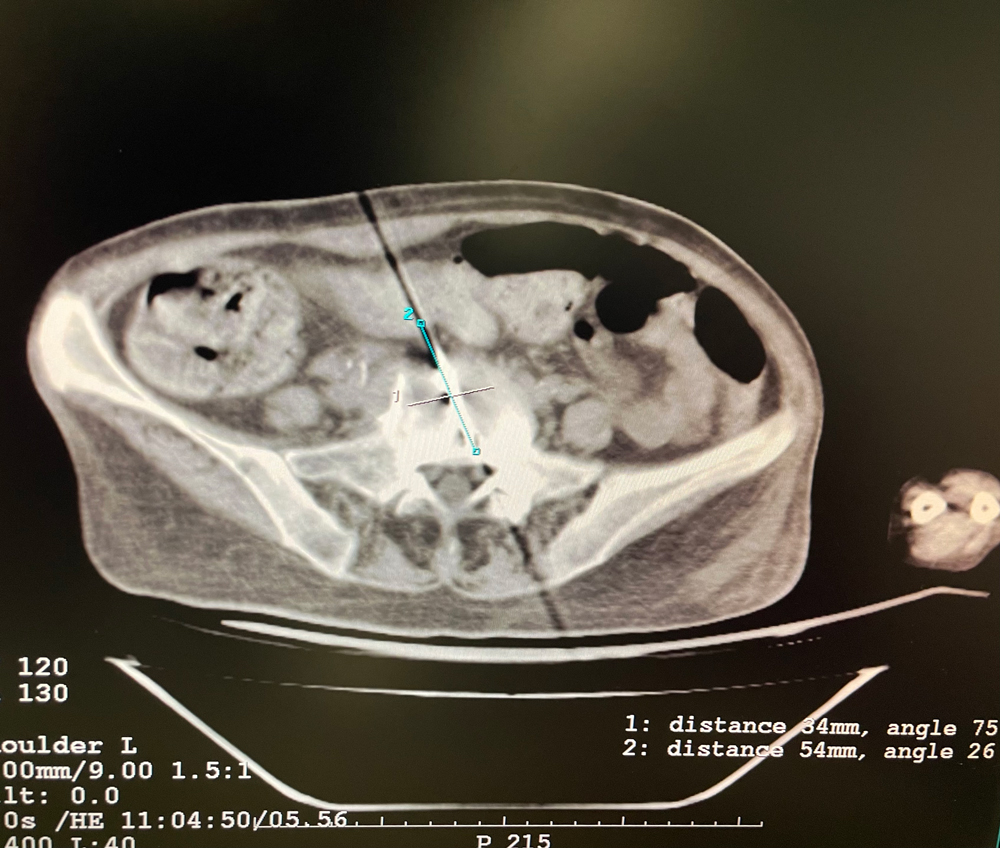

女,56歲,肺轉(zhuǎn)移瘤,骶骨、左側(cè)肋骨各一轉(zhuǎn)移灶,病灶大小均為5cm。骶骨轉(zhuǎn)移灶、肋骨轉(zhuǎn)移灶各進(jìn)行2個凍融循環(huán)。患者術(shù)后狀況良好。